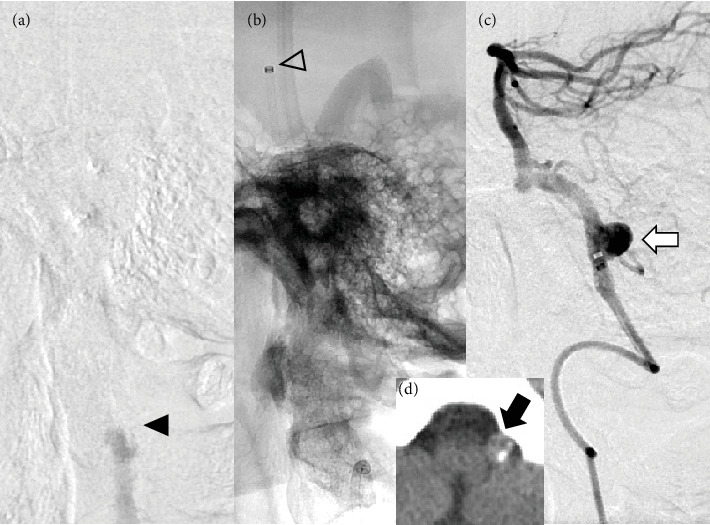

目的:随着机械取栓术(MT)在大血管闭塞性卒中中的应用越来越普遍,在MT靶血管中发现未破裂脑动脉瘤(uANs)的情况越来越多,需要通过病例积累来建立此类病例的MT安全指南。在这项研究中,我们的目的是回顾和报告我院与MT靶血管相关的uAN病例。方法:在2018年1月至2021年12月期间,我院320例大血管闭塞性卒中患者中,我们选择了在MT靶血管中有uAN的患者,并分析了各种参数,包括闭塞的血管、uAN位置、uAN发现时间、血栓取出程序、材料、再通结果和uAN破裂发生率。结果:320例患者中,7例发生靶血管动脉瘤(2.2%)。其中4例在器械穿过闭塞病变(病变交叉(LC))之前识别出病变,3例在LC或再通后识别出病变。在回顾性回顾中,3例中有1例在术前计算机断层扫描中怀疑有uAN。取栓程序包括1例患者单独直接抽吸首次通过技术(ADAPT), 2例患者单独支架置入术(SR), 3例患者联合治疗,1例患者SR联合尿激酶局部输注。有效再通率(定义为TICI 2b或3)为57.1%(4/7)。平均穿刺到再通时间为77.4分钟,没有一例与MT相关的uAN破裂。结论:我们报道了7例MT靶血管中的uAN。虽然我们采用了与常规MT相同的策略和技术,优先考虑再通,但没有uAN破裂与MT相关。术前图像评估更重要的是考虑到在MT靶血管中存在uAN的可能性,以及根据每个患者的情况仔细选择MT程序。

Objective: With the increasing prevalence of mechanical thrombectomy (MT) for large vessel occlusion strokes, encountering unruptured cerebral aneurysms (uANs) in MT target vessels has become more common, necessitating case accumulation to establish safety guidelines for MT in such cases. In this study, we aimed to review and present cases of uAN associated with MT target vessels at our hospital. Methods: Among 320 patients who underwent MT for large vessel occlusion strokes at our hospital between January 2018 and December 2021, we selected patients with uAN in the MT target vessel and analyzed various parameters including the occluded vessel, uAN location, timing of uAN discovery, thrombus retrieval procedures, materials, recanalization outcomes, and uAN rupture incidence. Results: Of the 320 patients, 7 had aneurysms in the target vessel (2.2%). The uANs were identified before the device crossed the occluded lesion (lesion crossing (LC)) in four cases, while in three cases, identification occurred after LC or recanalization. In 1 of the 3 cases, a uAN was suspected on preoperative computed tomography at the retrospective review. The thrombectomy procedures included a direct aspiration first pass technique (ADAPT) alone in one patient, stent retrieval (SR) alone in two patients, combination therapy in three patients, and SR combined with local infusion of urokinase in one patient. The effective recanalization rate, defined as TICI 2b or 3, was 57.1% (4/7). The average puncture-to-recanalization time was 77.4 min, and there were no instances of uAN rupture associated with MT. Conclusions: We presented seven cases of uAN in the MT target vessel. No uAN rupture was associated with MT, although the same strategies and techniques of routine MT at our hospital were employed, prioritizing recanalization. Preoperative image assessment considering the possibility of a uAN being present in the MT target vessel is more essential, as well as careful selection of MT procedures according to the situation of each patient.